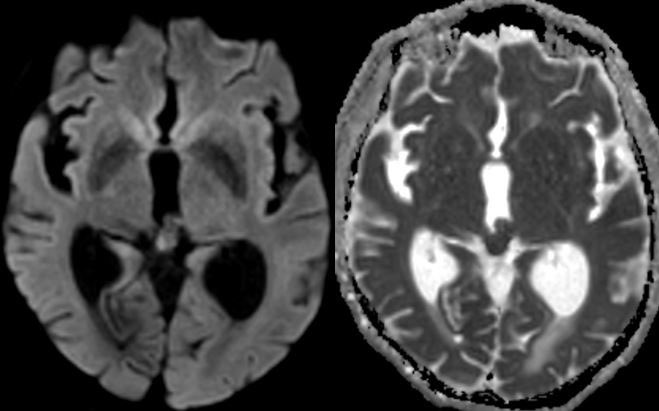

80 y/o patient presenting w/ headache is found to have a pineal mass and hydrocephalus. What is the most likely diagnosis and cause of the hydrocephalus?